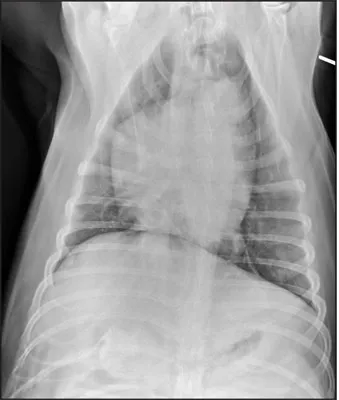

CASE 1.1 A 7-year-old neutered male Labrador Retriever who was hit by a car. You obtain these thoracic radiographs: Figs. 1.1a, b, left and right lateral projections, respectively; Figs. 1.1c, d, ventrodorsal and dorsoventral projections, respectively.

1.1c